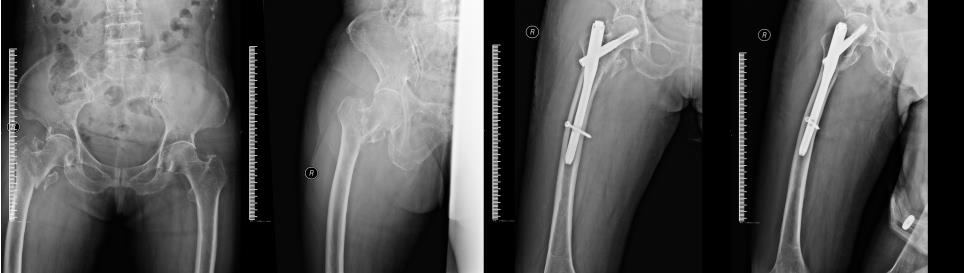

玉林市中西医结合骨科医院——骨病骨肿瘤股骨头坏死专科,是全国股骨头坏死保髋联盟成员单位,玉林市中医重点专科建设单位,是广西区内较早成立的、专注于股骨头坏死、骨病与骨肿瘤的特色科室。科室深耕上述疾病领域多年,始终恪守“精准诊疗、微创为先、中西结合”的理念,吸引了大量区内外患者慕名求医,每年开展的髋关节置换手术超千台,以精湛技术为众多患者重塑行走希望。

科室配备有专业的DAA关节置换工具、微创保髋工具、针对早期股骨头坏死的专业冲击波一体机、可用于清除骨肿瘤的超高转速磨钻等专业仪器,为病人治疗提供了强有力的硬件支持。